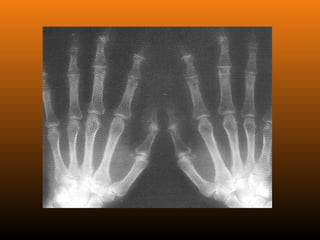

EROSIVA:Também conhecida como osteoartrose inflamatória.

reumatóide negativo)

RADIOLOGIA

No início da doença não se observam anormalidades. Com seu

desenvolvimento, observam-se:

 Diminuição do espaço intra-articular

 Esclerose subcondral (eburnação)

 Osteófitos;

 Erosão e anquilose óssea (pseudocistos ósseos).

PRIMÁRIA (idiopática): Ocorrena ausência de qualquer fator predisponente conhecido e se subdivide em duas categorias, localizada e generalizada (inclui 3 ou mais áreas). SECUNDÁRIA: É aquela em que se reconhece uma causa ou um fator preexistente. EROSIVA:Também conhecida como osteoartrose inflamatória. Acomete as articulações IFD e IFP nas mãos, com FR (fator reumatóide negativo) ClassificaçãoClassificação